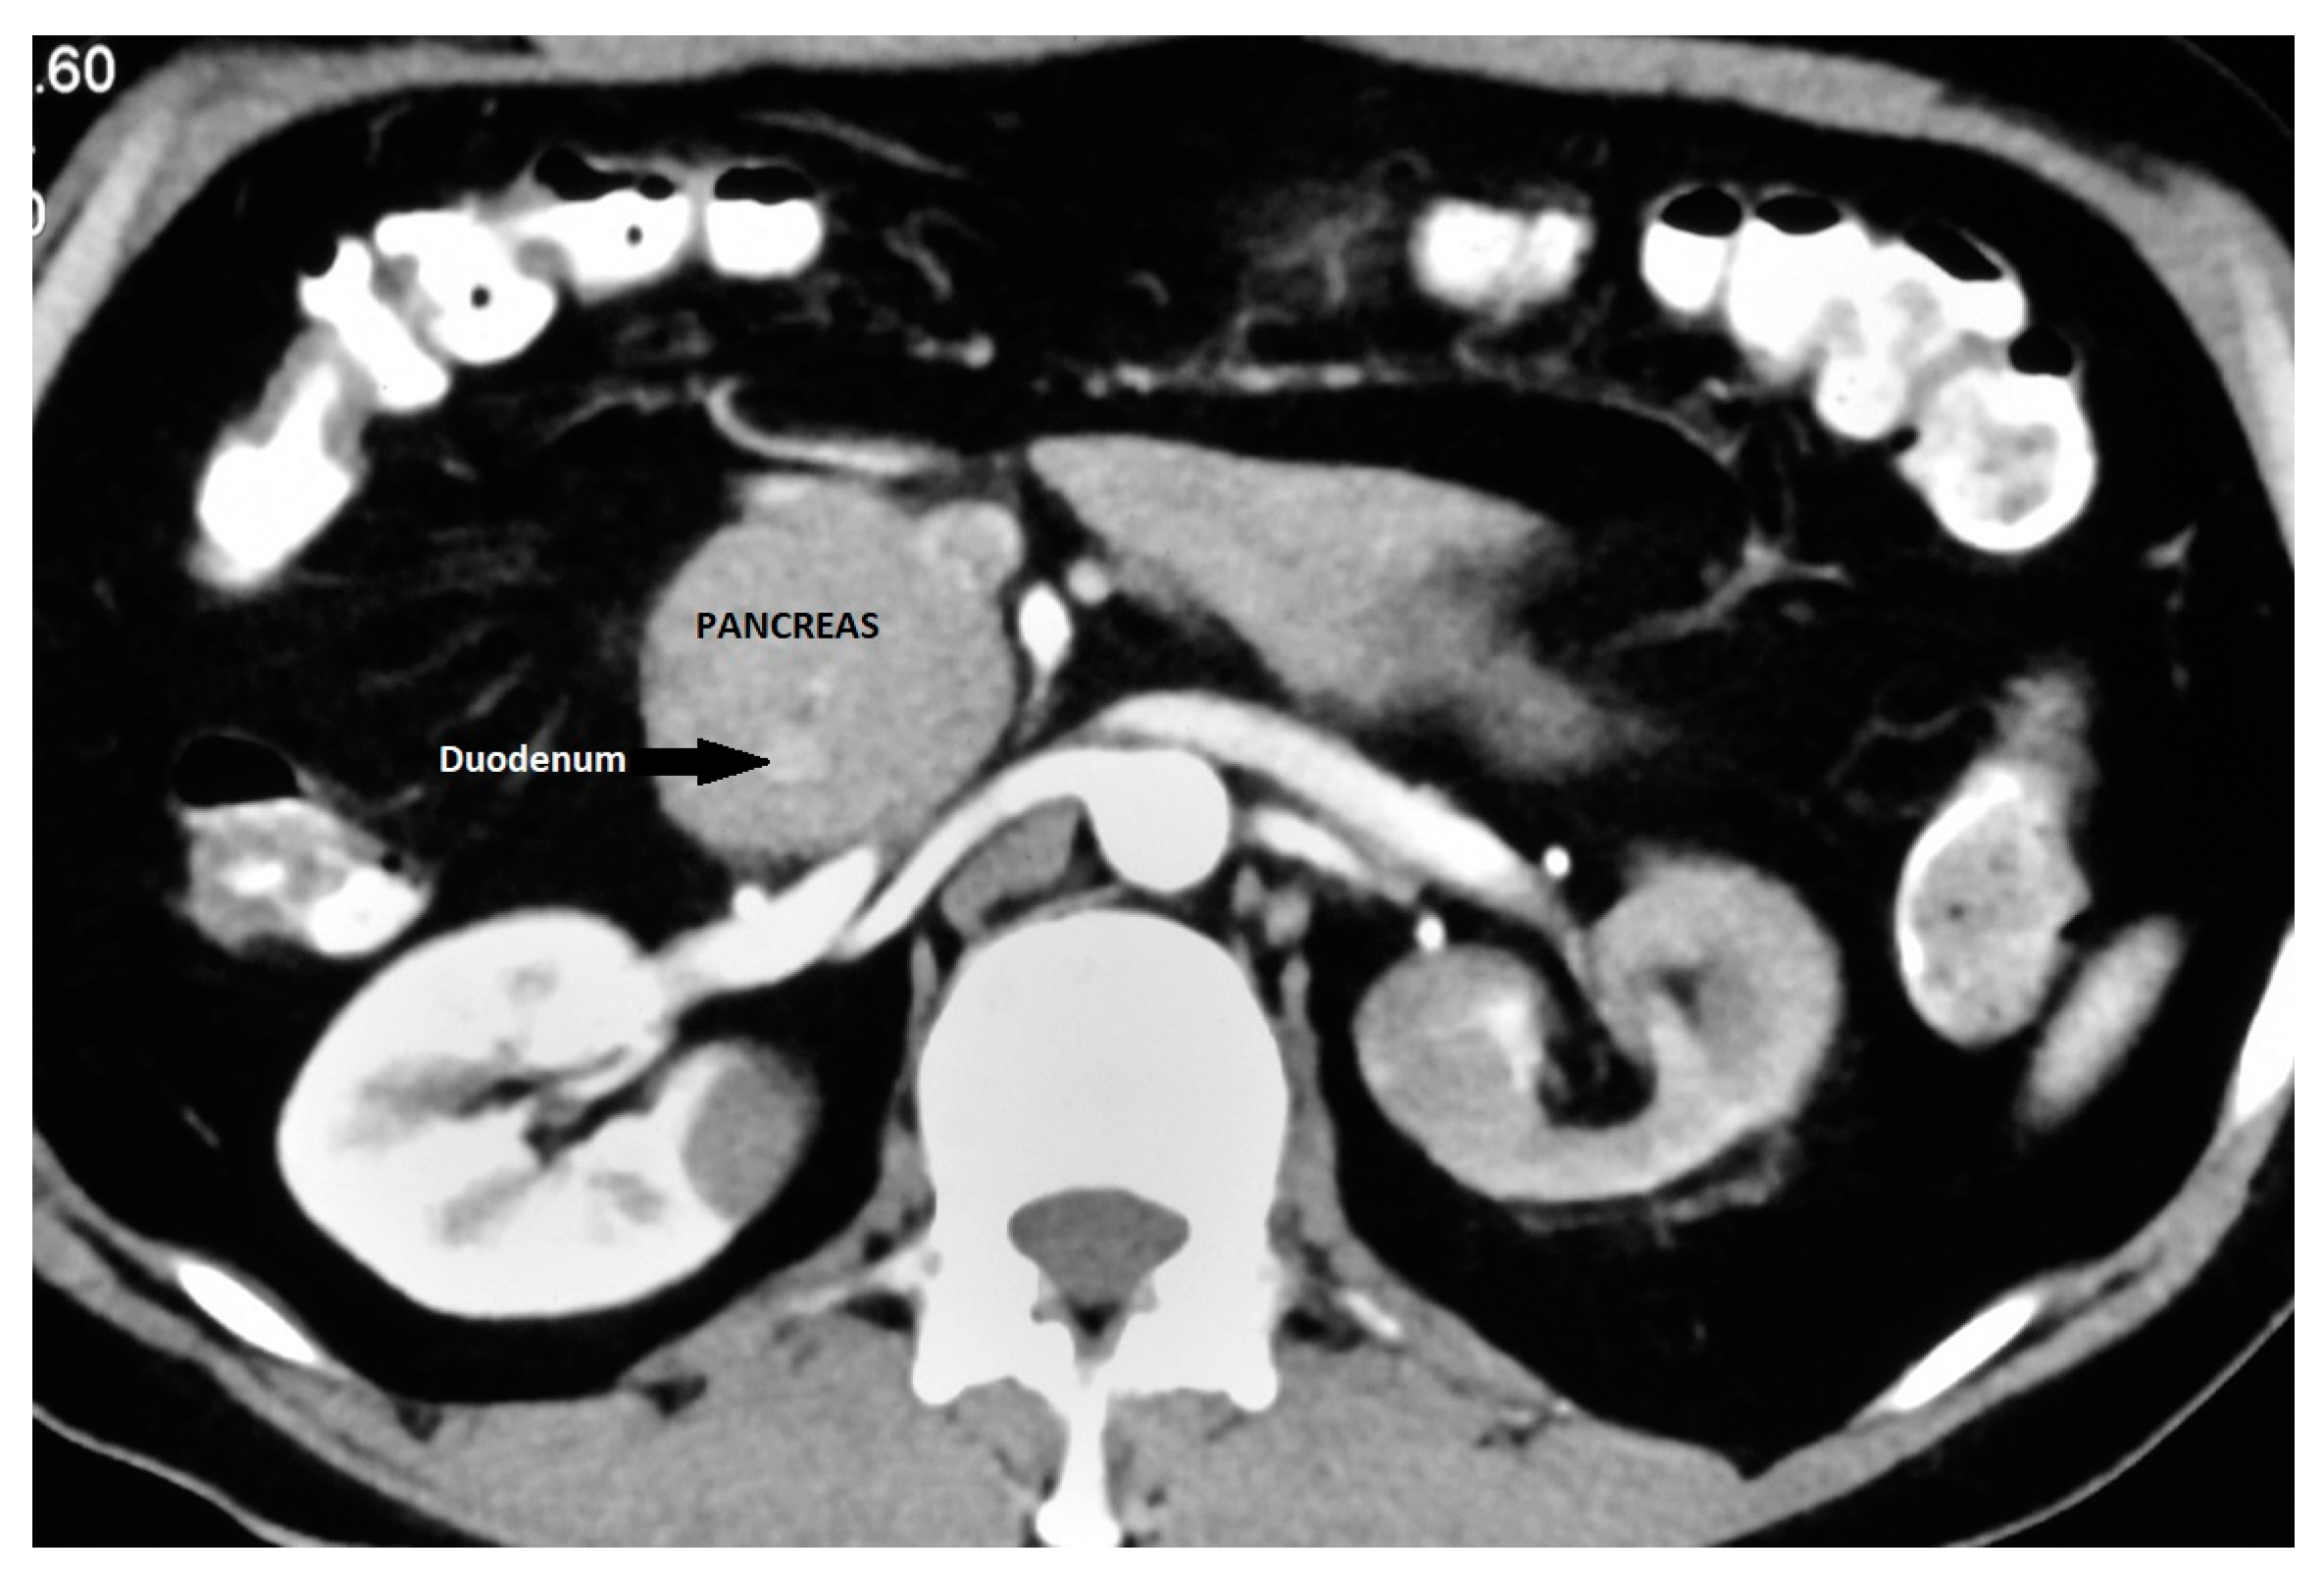

It is an important differential diagnosis for descending duodenal obstruction and a contrast-enhanced CT can demonstrate the enhancing pancreatic tissue around the duodenum (Figure 5) [41]. ERCP is considered as the gold standard for the diagnosis of AP as it provides visualization of the descending duodenum and the pancreatic ductal system along with the major and minor papilla [42,43]. Duodenal narrowing is usually located just proximal to the major papilla, and the minor papilla is usually situated at the proximal rim of the annular ring. In the majority of patients, the duct of the annular pancreas communicates with the main pancreatic duct arising from the major papilla. However, ERCP via the major papilla will not be able to diagnose AP in patients where the annular duct opens into the minor papilla or directly into the duodenum [44]. Moreover, ERCP is technically difficult in patients with significant duodenal obstruction. The annular duct can also be detected on MRCP, where it commonly connects with the main pancreatic duct near the major papilla but also may drain into the dorsal duct near the minor papilla or directly drain into the duodenum [45]. MRCP, apart from being non-invasive and operator-independent, can also visualize pancreatic parenchyma around the duodenum.

Figure 5.

Annular pancreas: CECT showing pancreatic tissue encircling descending duodenum.